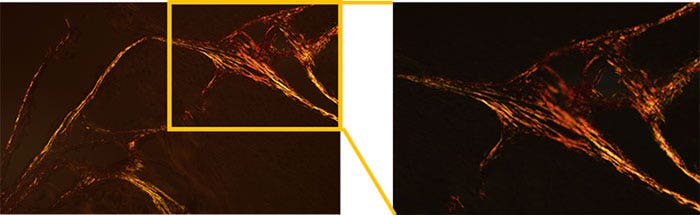

Figura 3: Imagen de muestra*

Figura 4: Resultados de medición

*El rojo muestra el tipo de colágeno I y el verde muestra el tipo de colágeno III